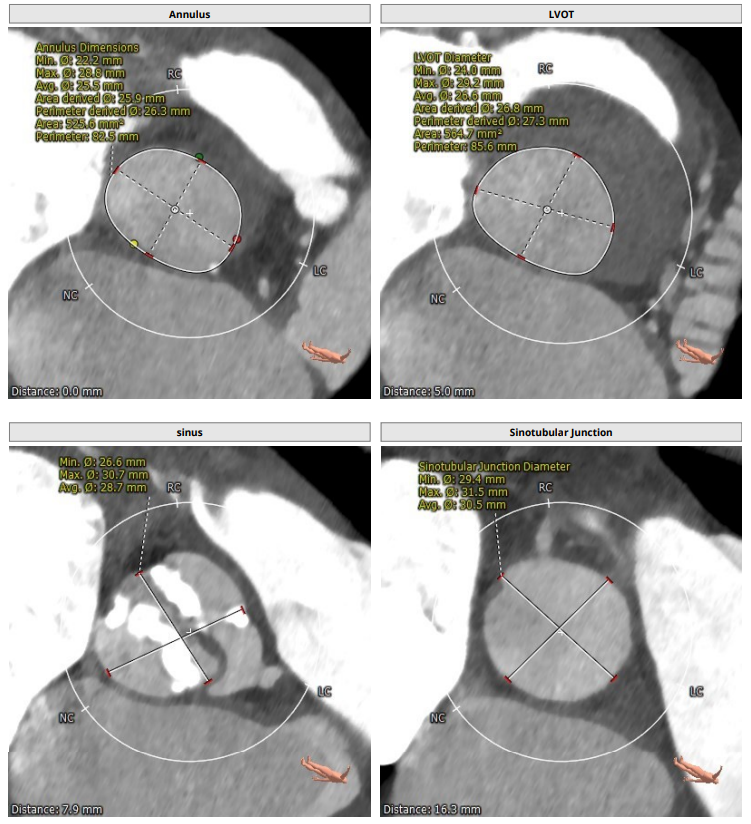

CT评估报告

入路评估:

双侧髂动脉直径窄,右侧髂总动脉可见钙化,遂选择颈动脉作为入路。

左侧颈动脉评估:

患者TYPE1型二叶瓣,左右冠窦可见融合,轻度钙化,瓣叶增厚,法式窦结构不大,双冠高度可,升主动脉未见明显增宽,横位心,心脏角度约67°,左室稍小,心肌肥厚,主动脉弓部走行较平缓,主动脉弓部可见钙化,过弓需谨慎,双侧髂动脉直径窄,右侧髂总动脉可见小夹层并可见环状钙化,左侧锁骨下动脉直径偏窄,双侧颈动脉直径符合入路条件,推荐左侧颈动脉做为主入路。